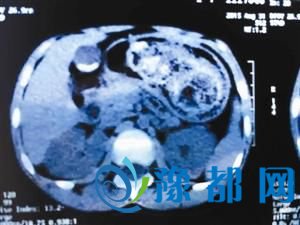

市儿童医院普外一科主任医师肖东介绍,诗诗入院时已经发展到吃不下东西,一吃就吐的程度。结合CT和胃镜检查,医生判断孩子患的是“异食症”导致的胃石梗阻。“头发在胃里很难消化,而且会和其他食物缠绕,时间一长,缠绕的越来越厉害,逐渐形成了巨大的胃石,最终堵塞胃肠道。”肖东表示,通过CT检查发现,石头已经占据了胃里90%的空间,无法通过胃镜取出来,只能通过手术取出胃石。